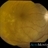

- progressive outer retinal necrosis (PORN)

- Fundus camera

- Fundus photography of an 38-year-old man diagnosed with PORN.